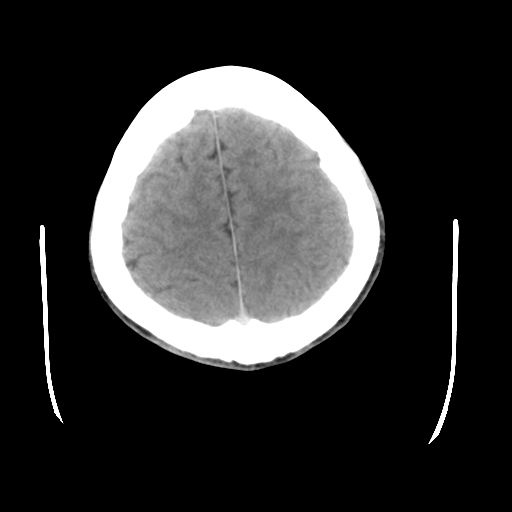

标题: CT23601:男, 17岁,剧烈头痛一小时。 [打印本页]

标题: CT23601:男, 17岁,剧烈头痛一小时。

男, 17岁,剧烈头痛一小时。